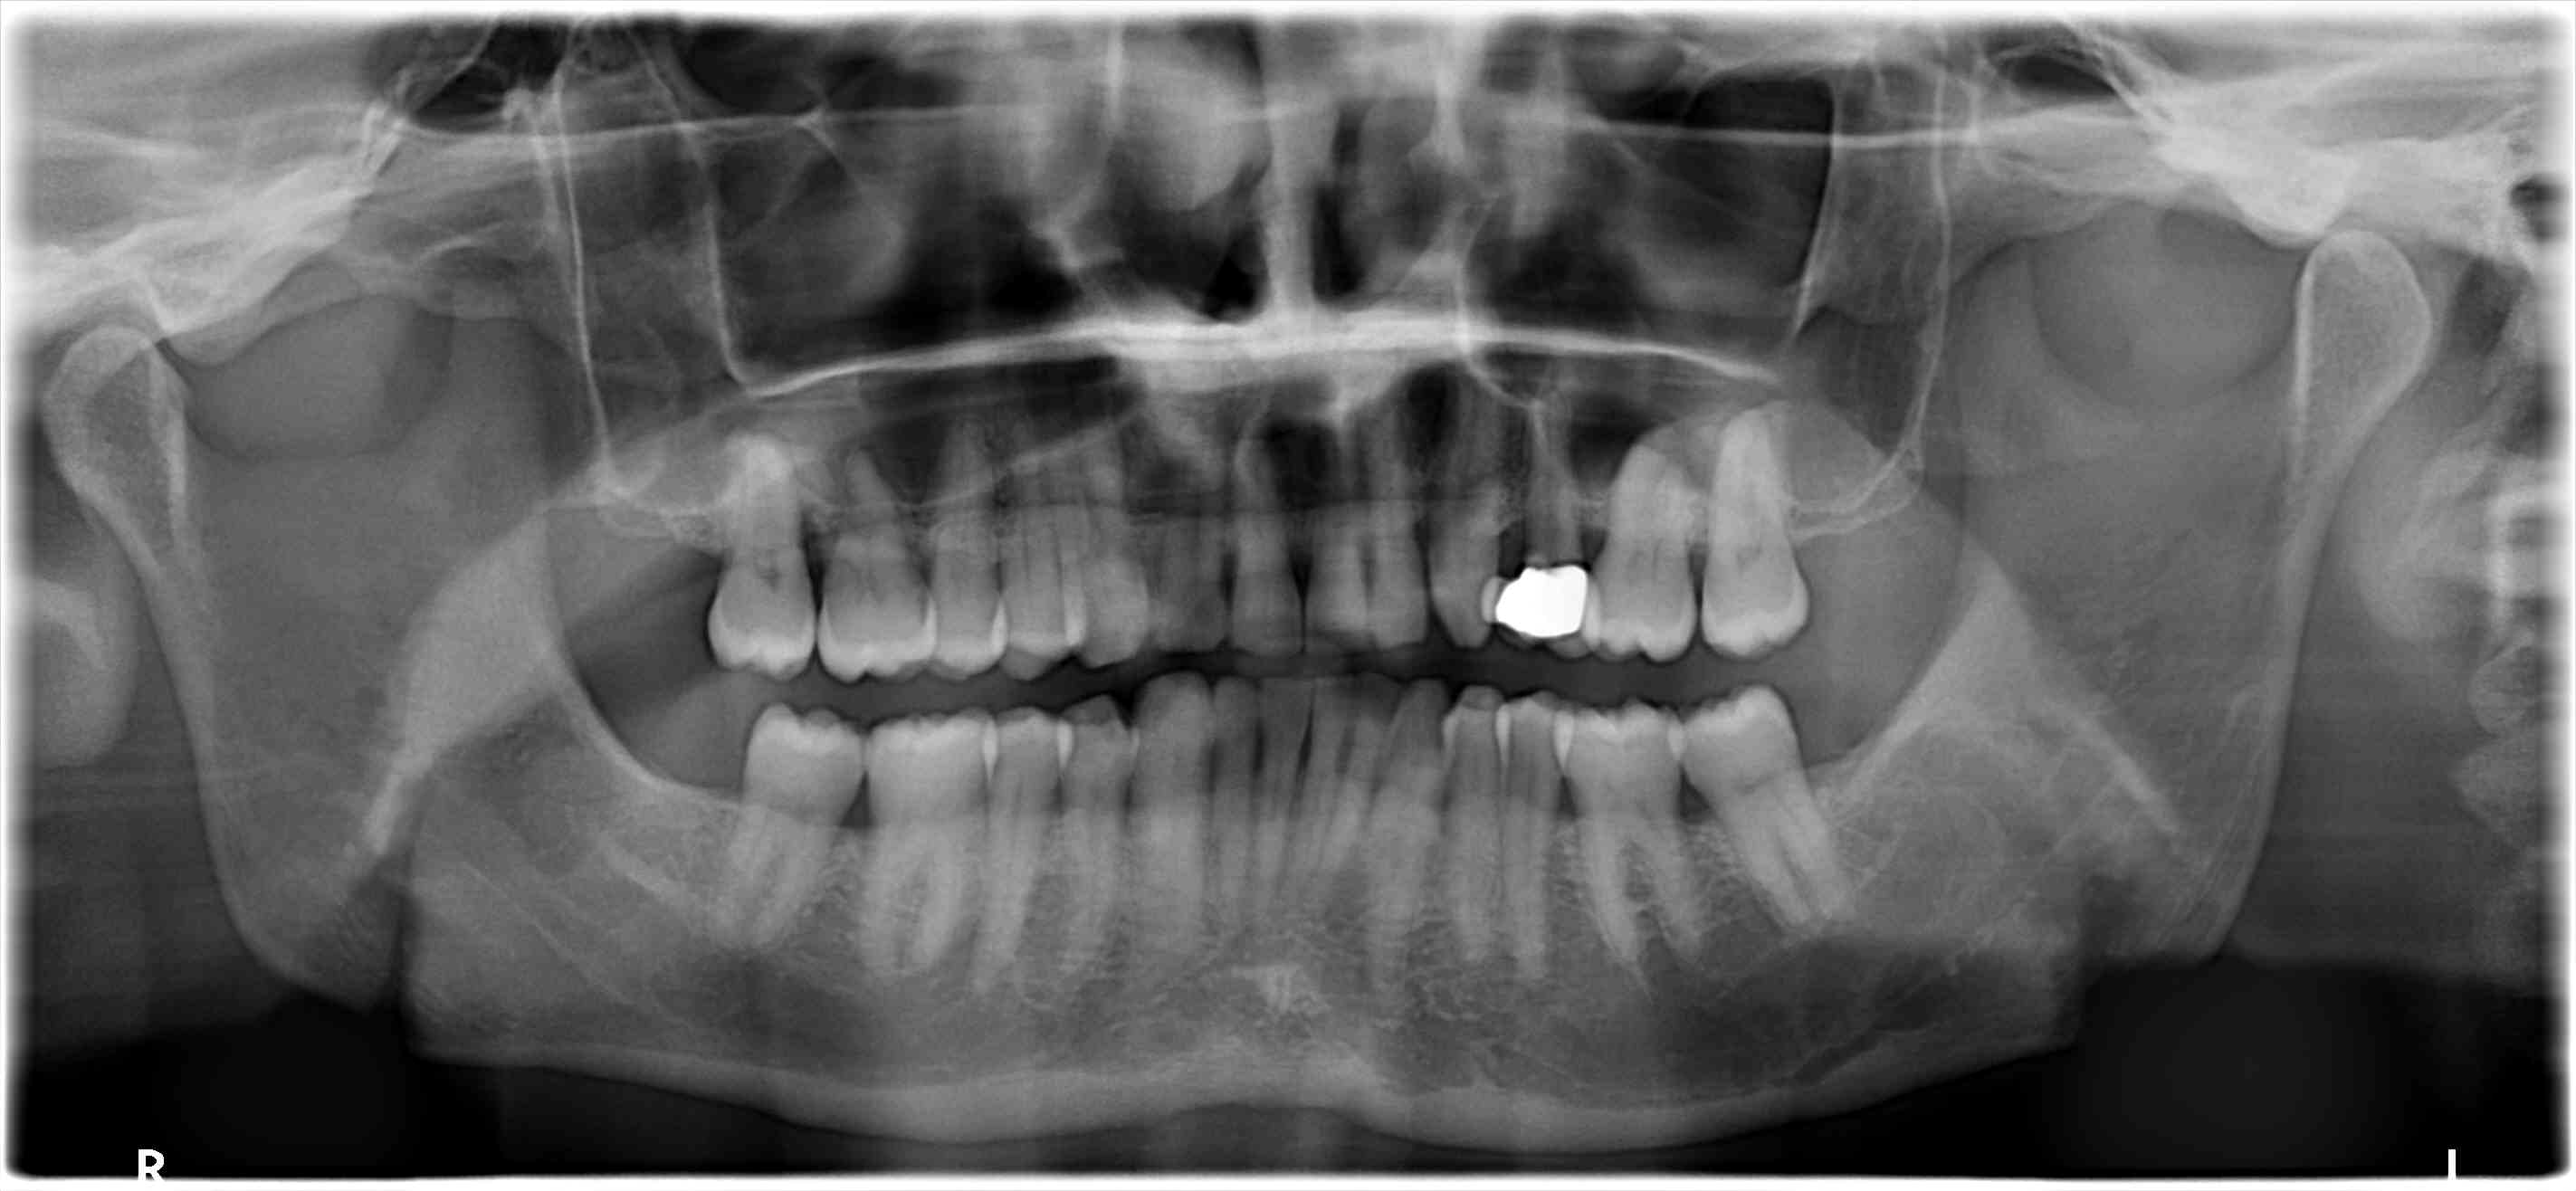

un patient 46 ans de longue date vient me voir pour la casse distale du bridge cantilever maxi gauche, fait sur dent vivante il y a 16 ans, réalisé après de l'ortho, la 14 a été extraite, avec un espace dispo entre 15-13 réduit.

De plus, avec un bilan paro correct,il trouve que les espaces surtout entre 46-47, 16-17 s'agrandissent et lui gênent de plus en plus.

bon bein, niveau ortho c'est pas le top... classe 2 secteur 2/3, limite classe 2 secteur 1/4...supraclusion...

Mais quand meme , on voit sur le haut , des plats d usure de 13 à 22 ET aussi , ce qui est interessant,2petits plats sur les pointes palatines de 17 et 27.

En bas tu t en doutes le pb vient de 33 , bien sur .

L ortho a été fait tardivement vers 20 ans pour des raisons esthêtiques. La 24 extraite mais semble t il , l ortho n a pas pu fermé l espace.

Mastication surtout droite pour êviter d abimer son bridge depuis des lustres.

Son guidage droit est plus simple , que le gauche.

Bruxisme je ne crois pas.

Posturalement, lordose-cyphose.